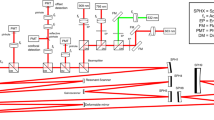

NIR-AF and SW-AF images were analyzed with a custom processing based on a modification of the method by Lois et al25,26. Semiquantitative autofluorescence plots were obtained using the publicly available Image J software (ImageJ 64 version 1.48q, Wayne Rasband, National Institutes of Health, Bethesda, MD, http://imagej.nih.gov/ij) and the “Radial profile angle” plugin (Philippe Carl, http://rsb.info.nih.gov/ij/plugins/radial-profile-ext.html), as illustrated in the Supplementary Figure 2. After conversion to 8-bit grayscale pictures, this plugin calculates mean gray intensity values along concentric circular lines. After visual identification of the fovea, two hemi-circular regions of interest of radius R (in pixels), centered on the fovea were defined, one on the temporal and one on the nasal side of the macula. R was determined as the maximum distance between the fovea and the optic disc or the temporal border of the picture (usually 160–200 pixels). Then the software extracted the mean grayscale pixel intensity for each nasal and temporal hemi-circle of radius 1 to R. After subtraction of the autofluorescence intensity reference AF ref , set manually on the optic nerve head, each grayscale intensity level AF measured for a radius r (from 1 to R) was divided by the mean grayscale intensity of the full autofluorescence image AF mean after subtraction of AF ref , in order to provide a normalized relative autofluorescence level AF (r), according to the following formula:

Finally, after pixel-to-degree conversion, relative autofluorescence intensities were exported to GraphPad Prism (version 5.0 f, GraphPad Software, La Jolla, CA, USA), and a combined graphical representation of averaged SW-AF and NIR-AF patterns of a single eye along hemicircular lines was plotted. The standard deviation interval of relative autofluorescence values acquired in the right eye of eight age-matched healthy subjects was also represented along with autofluorescence plots of each investigated eye.

Structural foveal alterations on horizontal SD-OCT scans through the fovea were categorized according to Sundaram et al.14, as stage 1, continuous inner segment ellipsoid band (ISe); stage 2, ISe disruption; stage 3, ISe absence; and stage 4, hyporeflective zone (HRZ) affecting outer retinal layers.

The average diameter of central fluorescence abnormalities on SW-AF and NIR-AF was measured in degrees using the semiquantitative autofluorescence plots by two independent observers (IA and AM) in a masked fashion. The extension of ISe defects on horizontal SD-OCT scans was measured independently on anonymized images by the two observers using the built-in caliper function of the Heidelberg Eye Explorer software (version 1.9.10.0). Each imaging parameter was measured twice by each observer, to assess intra-observer agreement, and the mean between both measures was used to assess inter-observer agreement. For statistical analyses, the mean between measures by the two observers was employed.